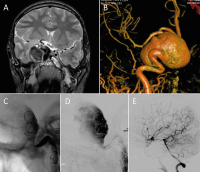

Neurovaskuläre Therapieoptionen bei komplexen Aneurysmen der Arteria carotis interna // Neurovascular therapeutic options in complex intracranial aneurysms

Journal für Neurologie, Neurochirurgie und Psychiatrie 2021; 22 (3): 128-134 Volltext (PDF) Summary Praxisrelevanz Abbildungen